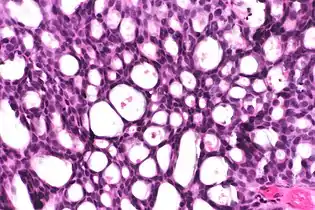

In myocardial infarction

After a myocardial infarction (heart attack), no histopathology is seen the first ~30 minutes. The only possible sign the first 4 hours is waviness of fibres at border. Later, however, a coagulation necrosis is initiated, with edema and hemorrhage. After 12 hours, there can be seen karyopyknosis and hypereosinophilia of myocytes with contraction band necrosis in margins, as well as beginning of neutrophil infiltration. At 1 – 3 days there is continued coagulation necrosis with loss of nuclei and striations and an increased infiltration of neutrophils to interstitium. Until the end of the first week after infarction there is beginning of disintegration of dead muscle fibres, necrosis of neutrophils and beginning of macrophage removal of dead cells at border, which increases the succeeding days. After a week there is also beginning of granulation tissue formation at margins, which matures during the following month, and gets increased collagen deposition and decreased cellularity until the myocardial scarring is fully mature at approximately 2 months after infarction.[3]